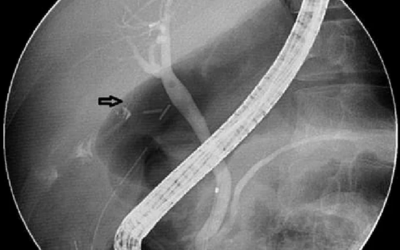

The stent can be installed endoscopically, with the help of ERCP (Endoscopic Retrograde Cholangiopancreatography), which is a procedure that implies inserting an endoscope through the mouth.

The endoscope will be inserted into the digestive tract to the bile duct where the stent will be placed.

The position of the stent is checked using imaging techniques like X-ray or fluoroscopy to ensure it's properly placed.